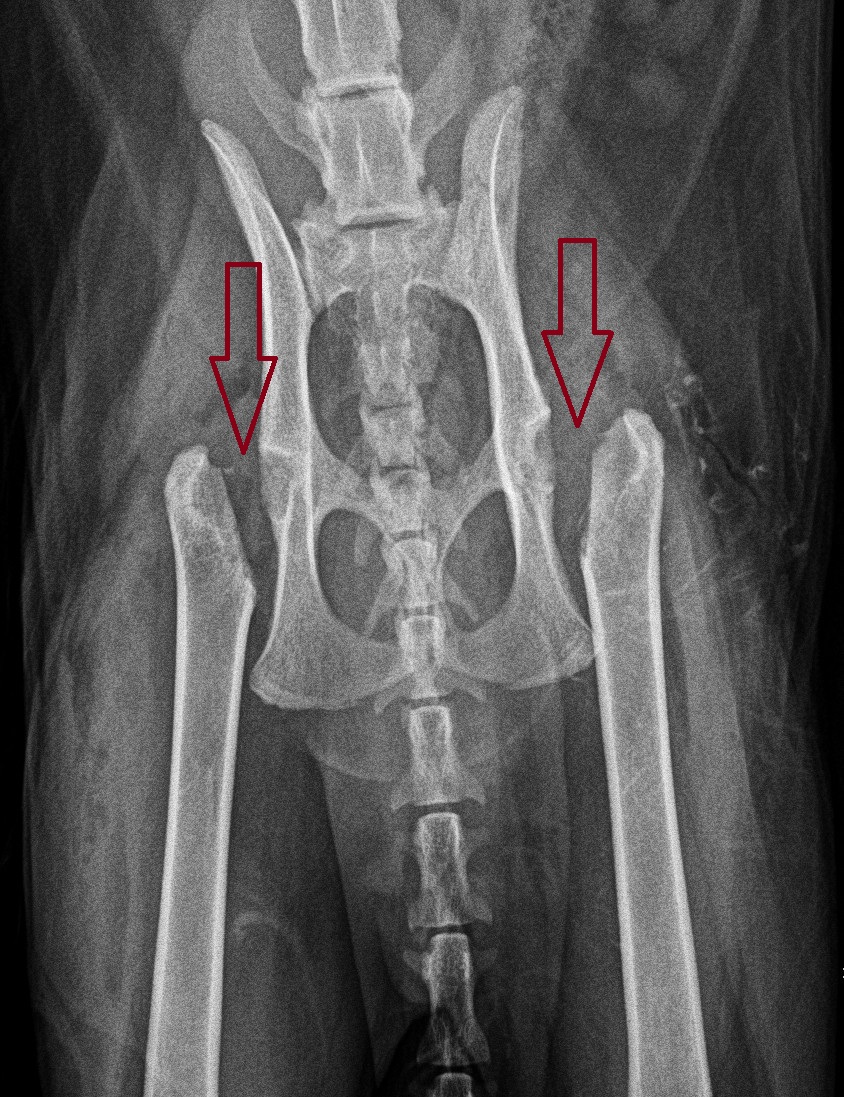

What is an FHO?

The treatment is a surgery called an FHO (Femoral Head Ostectomy), where the ball of the hip is removed. Then the ligament around the hip is sutured to provide padding. Over the following 2 months, scar tissue builds up around the hip “joint”.

We don’t love doing both sides at the same time. There are medical & financial pros and cons for doing the FHOs at the same time or over a few months.

Atlas’ owner remembers: “I’m glad we were able to do both hips at once, as the recovery was not easy. I’m glad we didn’t have to go through it twice.”

So our kitty had surgery, which was uneventful. After 1 night in the hospital on IV fluids, antibiotics and pain medications, he went home the following day.